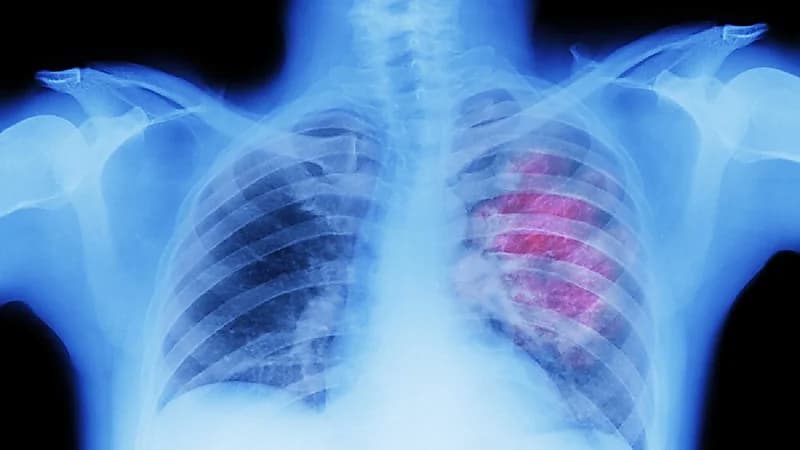

كشفت دراسة جديدة، أن فيروس كورونا يمكن أن ينتشر في غضون أيام من الشعب الهوائية إلى القلب والدماغ وتقريباً كل عضو في الجسم.

ووجد الفريق أن العامل المسبب للمرض في الفيروس قادر على التكاثر في الخلايا البشرية كلها، وليس فقط بالجهاز التنفسي، والبقاء بها لأشهر.

وأضاف الباحثون: "تُظهر نتائجنا بشكل جماعي أنه في حين أن العبء الأكبر لفيروس كورونا يقع في الشعب الهوائية والرئة، يمكن للفيروس أن ينتشر مبكراً أثناء العدوى ويصيب الخلايا في جميع أنحاء الجسم، بما في ذلك الدماغ"